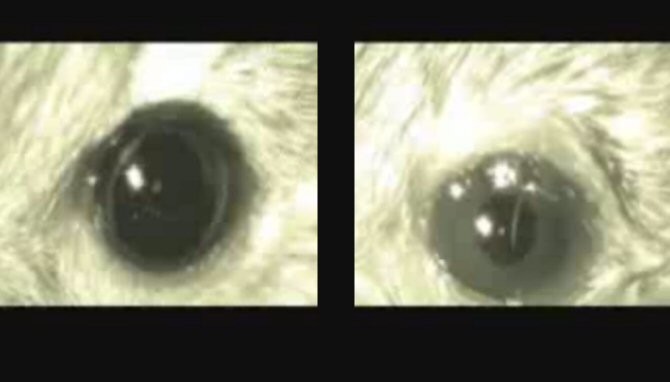

La sustancia, llamada AAQ, hace que otras células de la retina, normalmente insensibles a la luz, se vuelvan sensibles a ella. La AAQ se enlaza a canales iónicos proteicos sobre la superficie de esas células retinales. En presencia de la luz, la sustancia altera el flujo de iones a través de los canales y activa esas células retinales de un modo bastante parecido a como nuestras células primarias para la visión (los conos y los bastoncillos) son activadas por la luz.![[Img #9471]](upload/img/periodico/img_9471.jpg)